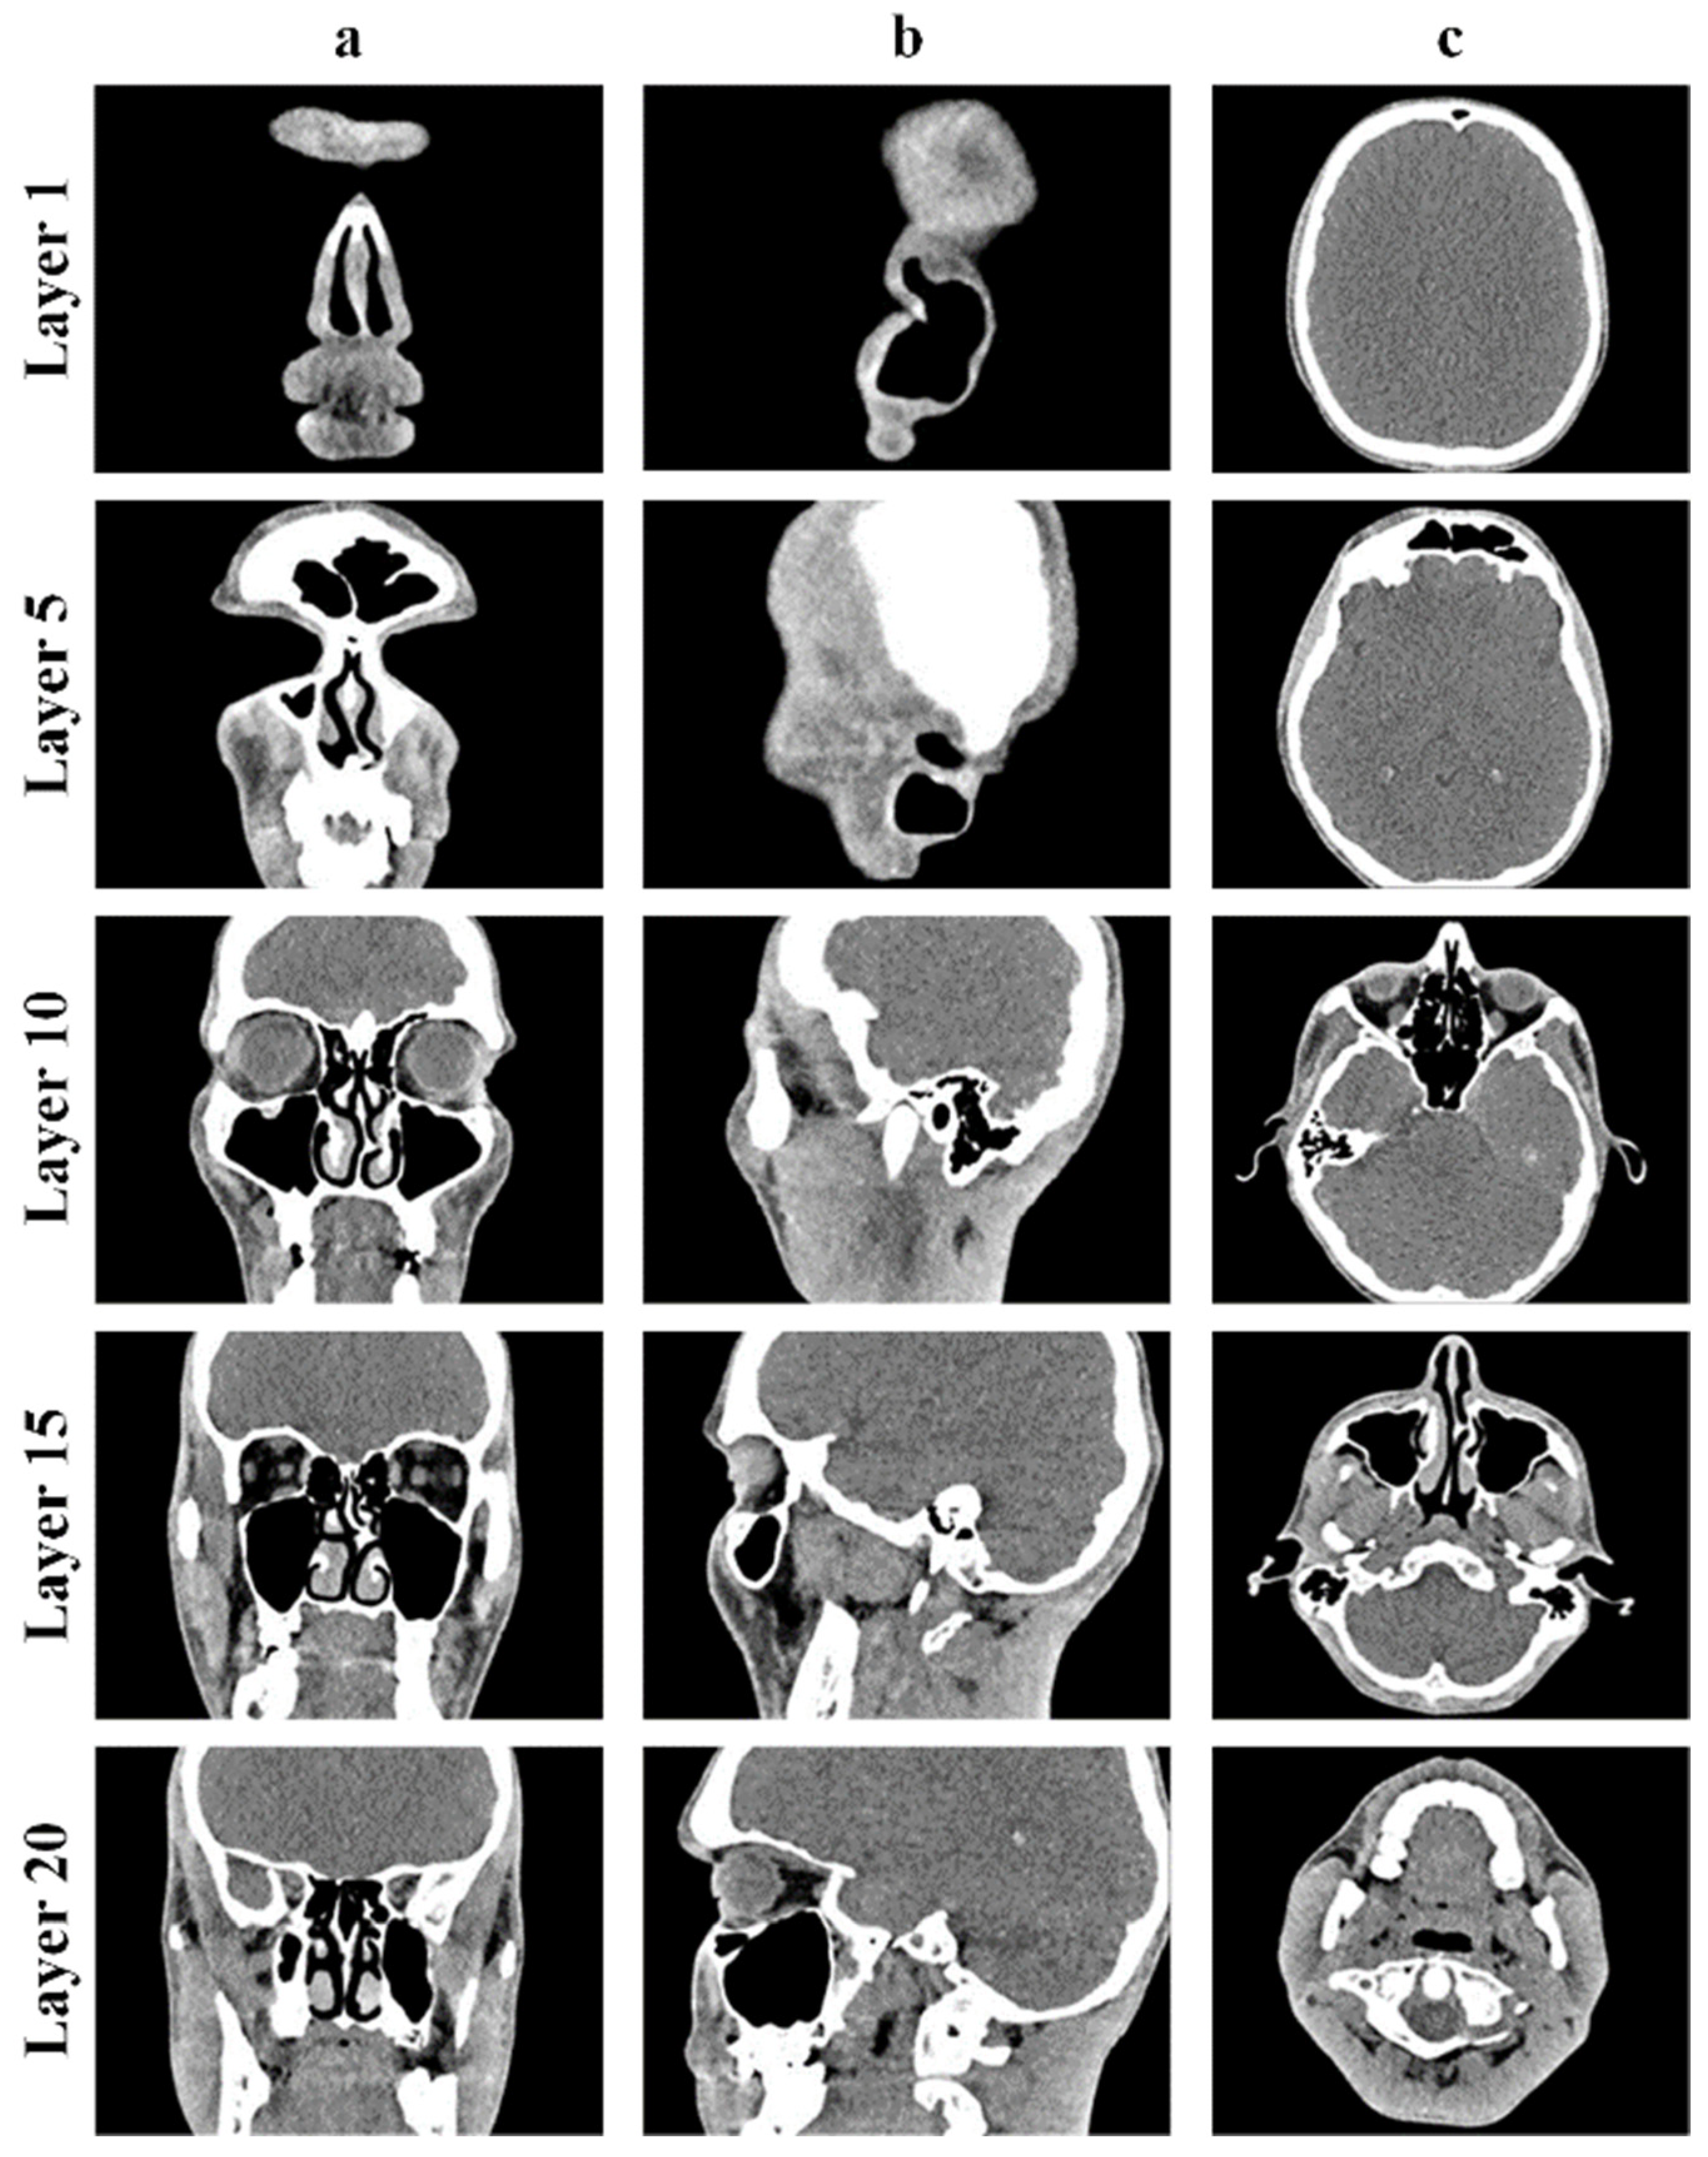

The obtained CT results for the upper respiratory tract, particularly the human nasal cavity, are depicted in Figure 1 across three distinct projections: frontal, sagittal, and axial planes.

The CT images above clearly show the boundaries between the airways (dark area of the CT images) and soft or bone tissue (light area of the CT images).

The construction of virtual models of the human nasal cavity and lungs is carried out by layer-by-layer processing of visualized CT images in three different planes using special computer programs aimed at constructing three-dimensional objects.

To generate a 3D model of the upper respiratory tract, CT images of the nasal cavity were loaded into the 3D Slicer program and displayed in three projections: frontal, sagittal, and axial (Figure 3).

Figure 1. CT results of the human nasal cavity: frontal plane (a); sagittal plane (b); axial plane (c).